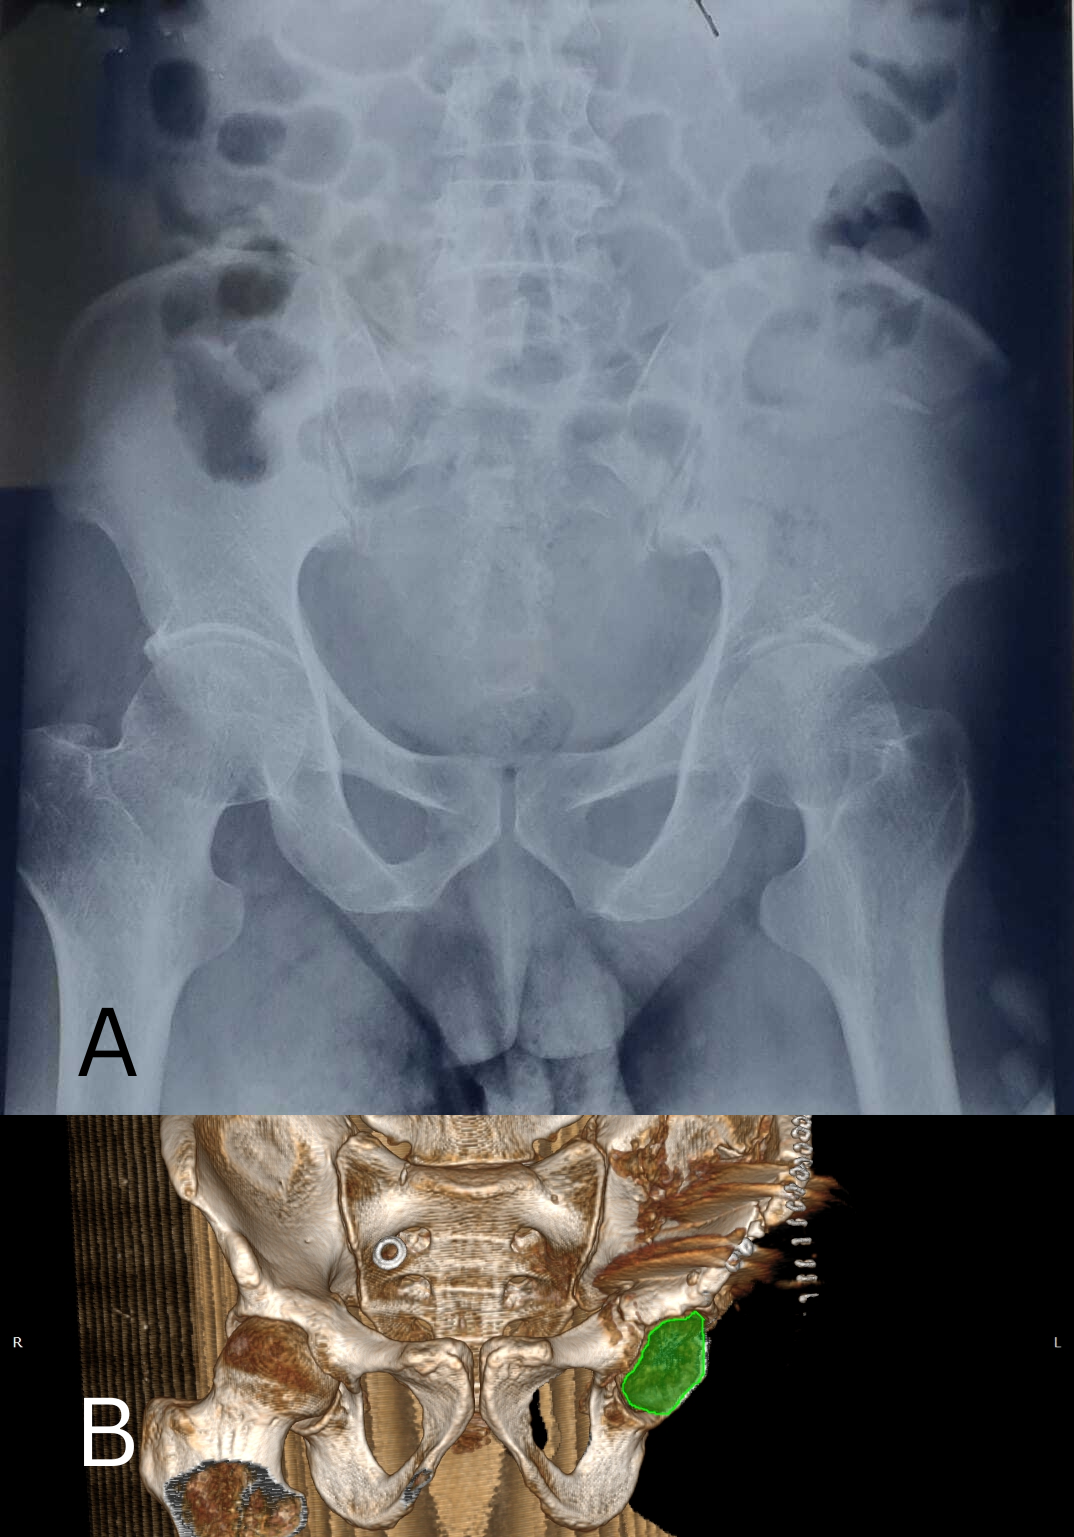

Besides this elementary displaced lesion, it was observed that the anterior, posterior and medial wall was part of the line (Fig. 3) with it being continuous with the voluminous upper fragment.

Figure 3: (a) Pre-operative antero-posterior X-ray of the acetabulum showing a superior type fracture of the right acetabulum (b) post operative 3D reconstruction of the pelvis showing superior fracture while respecting continuity of the pelvic ring.

Computed tomography (CT) showed separation of the anterior wall of the cranial fragment by a slightly displaced split line (Fig. 4 and 5).